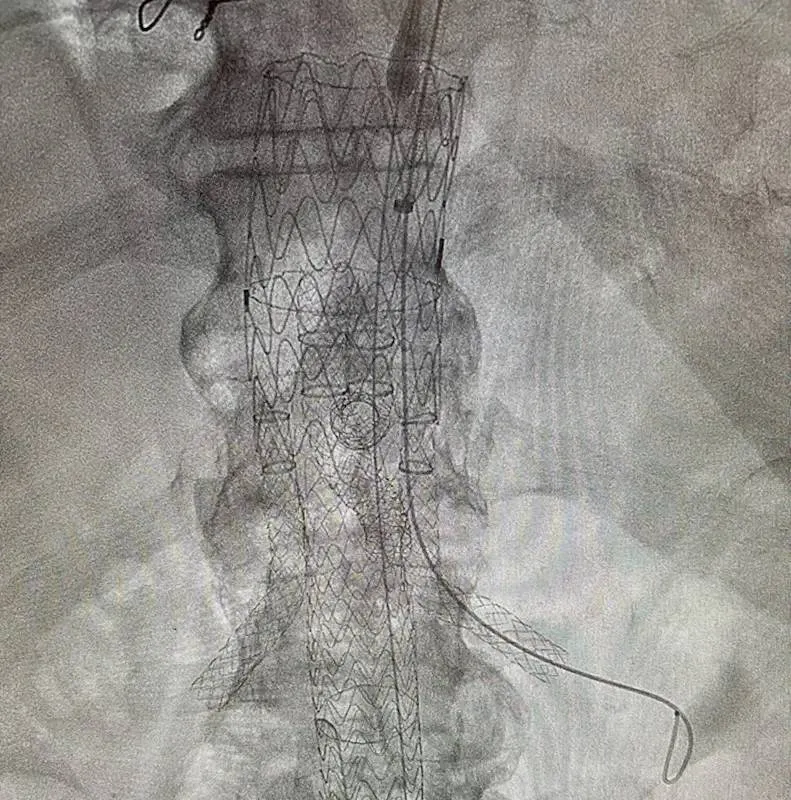

TILBURG – Het Elisabeth-TweeSteden Ziekenhuis (ETZ) heeft als eerste ziekenhuis in Europa drie operaties uitgevoerd met een nieuwe stent voor de grote slagader in de buik. De innovatieve stent biedt uitkomst voor patiënten met een uitstulping in de grote bloedvaten van borst en buik, een ernstige en complexe aandoening.

Bij patiënten met een uitstulping in de aorta plaatsen chirurgen vaak een stent die speciaal op maat gemaakt is. Het ontwerpen en produceren van zo’n stent neemt normaal tot twaalf weken in beslag. In die periode wachten patiënten op hun behandeling, terwijl de aandoening risico’s met zich meebrengt.

De nieuwe stent heeft een standaardontwerp en ligt direct op voorraad. Daardoor start de behandeling veel sneller. Patiënten krijgen eerder duidelijkheid en ervaren minder spanning in de periode voorafgaand aan de operatie.